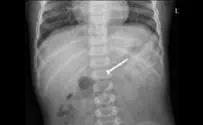

בבית-החולים רמב"ם בחיפה נולדו בסוף-השבוע האחרון שבעה זוגות תאומים ושלישיה אחת. שיא ילודה שלא זכור כמותו במחלקת היולדות בביה"ח.